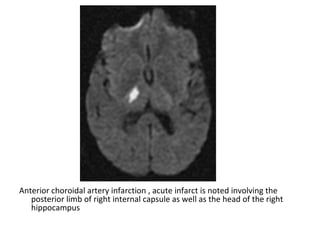

-The anterior choroidal artery is the most distal

Anterior choroidal artery infarction , acute infarct is noted involving the

posterior limb of right internal capsule as well as the head of the right

hippocampus